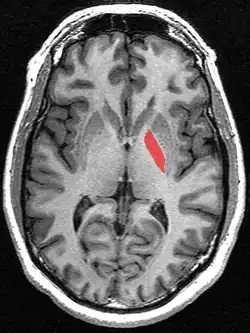

![]() Globus pallidus (in red) shown within the brain | |

The globus pallidus (GP), also known as paleostriatum or dorsal pallidum,[1] is a major component of the subcortical basal ganglia in the brain. It consists of two adjacent segments, one external (or lateral), known in rodents simply as the globus pallidus, and one internal (or medial). It is part of the telencephalon, but retains close functional ties with the subthalamus in the diencephalon – both of which are part of the extrapyramidal motor system.[2]